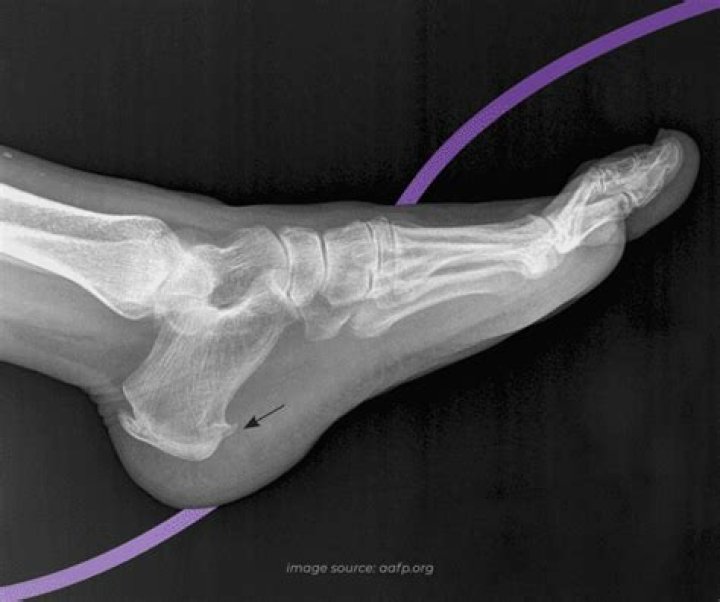

Introduction. The anode heel effect in radiography is a well-described physical phenomenon,1,2 whereby radiation intensity varies along the anode–cathode axis of the X-ray tube, decreasing towards the anode. Photons emitted towards the tube’s anode side are attenuated more than those emitted towards the cathode.

The anode heel effect is the variation in x-ray intensity along the longitudinal axis of the tube. It’s called the anode heel effect because photons formed deeper in the anode must first pass through the “heel” of the anode which causes that “side” to lose intensity before reaching the object or image receptor.

The Heel effect causes a Gaussian distribution around the anode–cathode axis and a logarithmic distribution parallel to this axis.